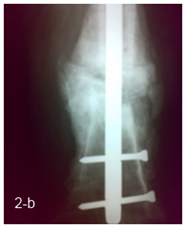

14 patients were operated by a 2 stage strategy including debridement at the fracture site through lateral approach with excision of all infected tissues and necrotic bone with no external fixation in the first session, then rest and parenteral antibiotic was given for 4 to 6 weeks and follow up with serial ESR & CRP were done before second session, 6 weeks after the first session; the second session was done through fixation by locked intra medullary nail with use of autogenous cancellous bone graft in patients with bone defects more than 2 cm (Figure 2 a, b).

Figure 2 a) Femoral infected non union after removal of implant in 1st stage. b) 2nd stage fixation by nail.